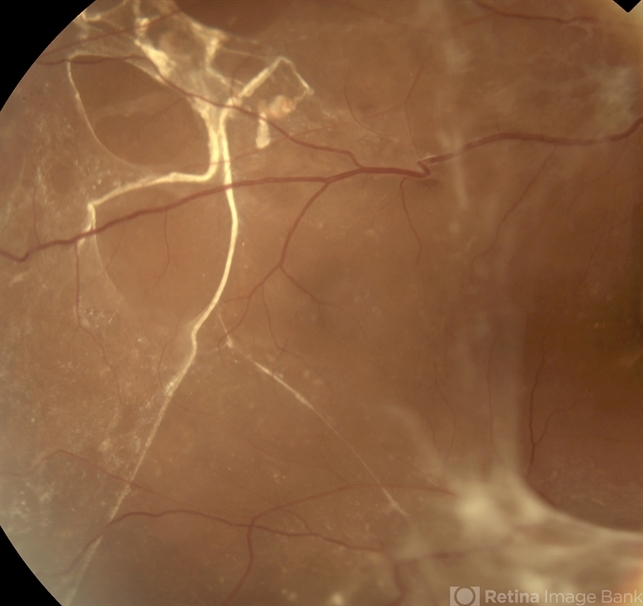

- proliferative diabetic retinopathy (PDR), tractional retinal detachment, subretinal bands

- Fundus photograph of a diabetic man with subretinal and pre-retinal bands and membranes associated with combined tractional rhegmatogenous retinal detachment due to proliferative diabetic retinopathy.